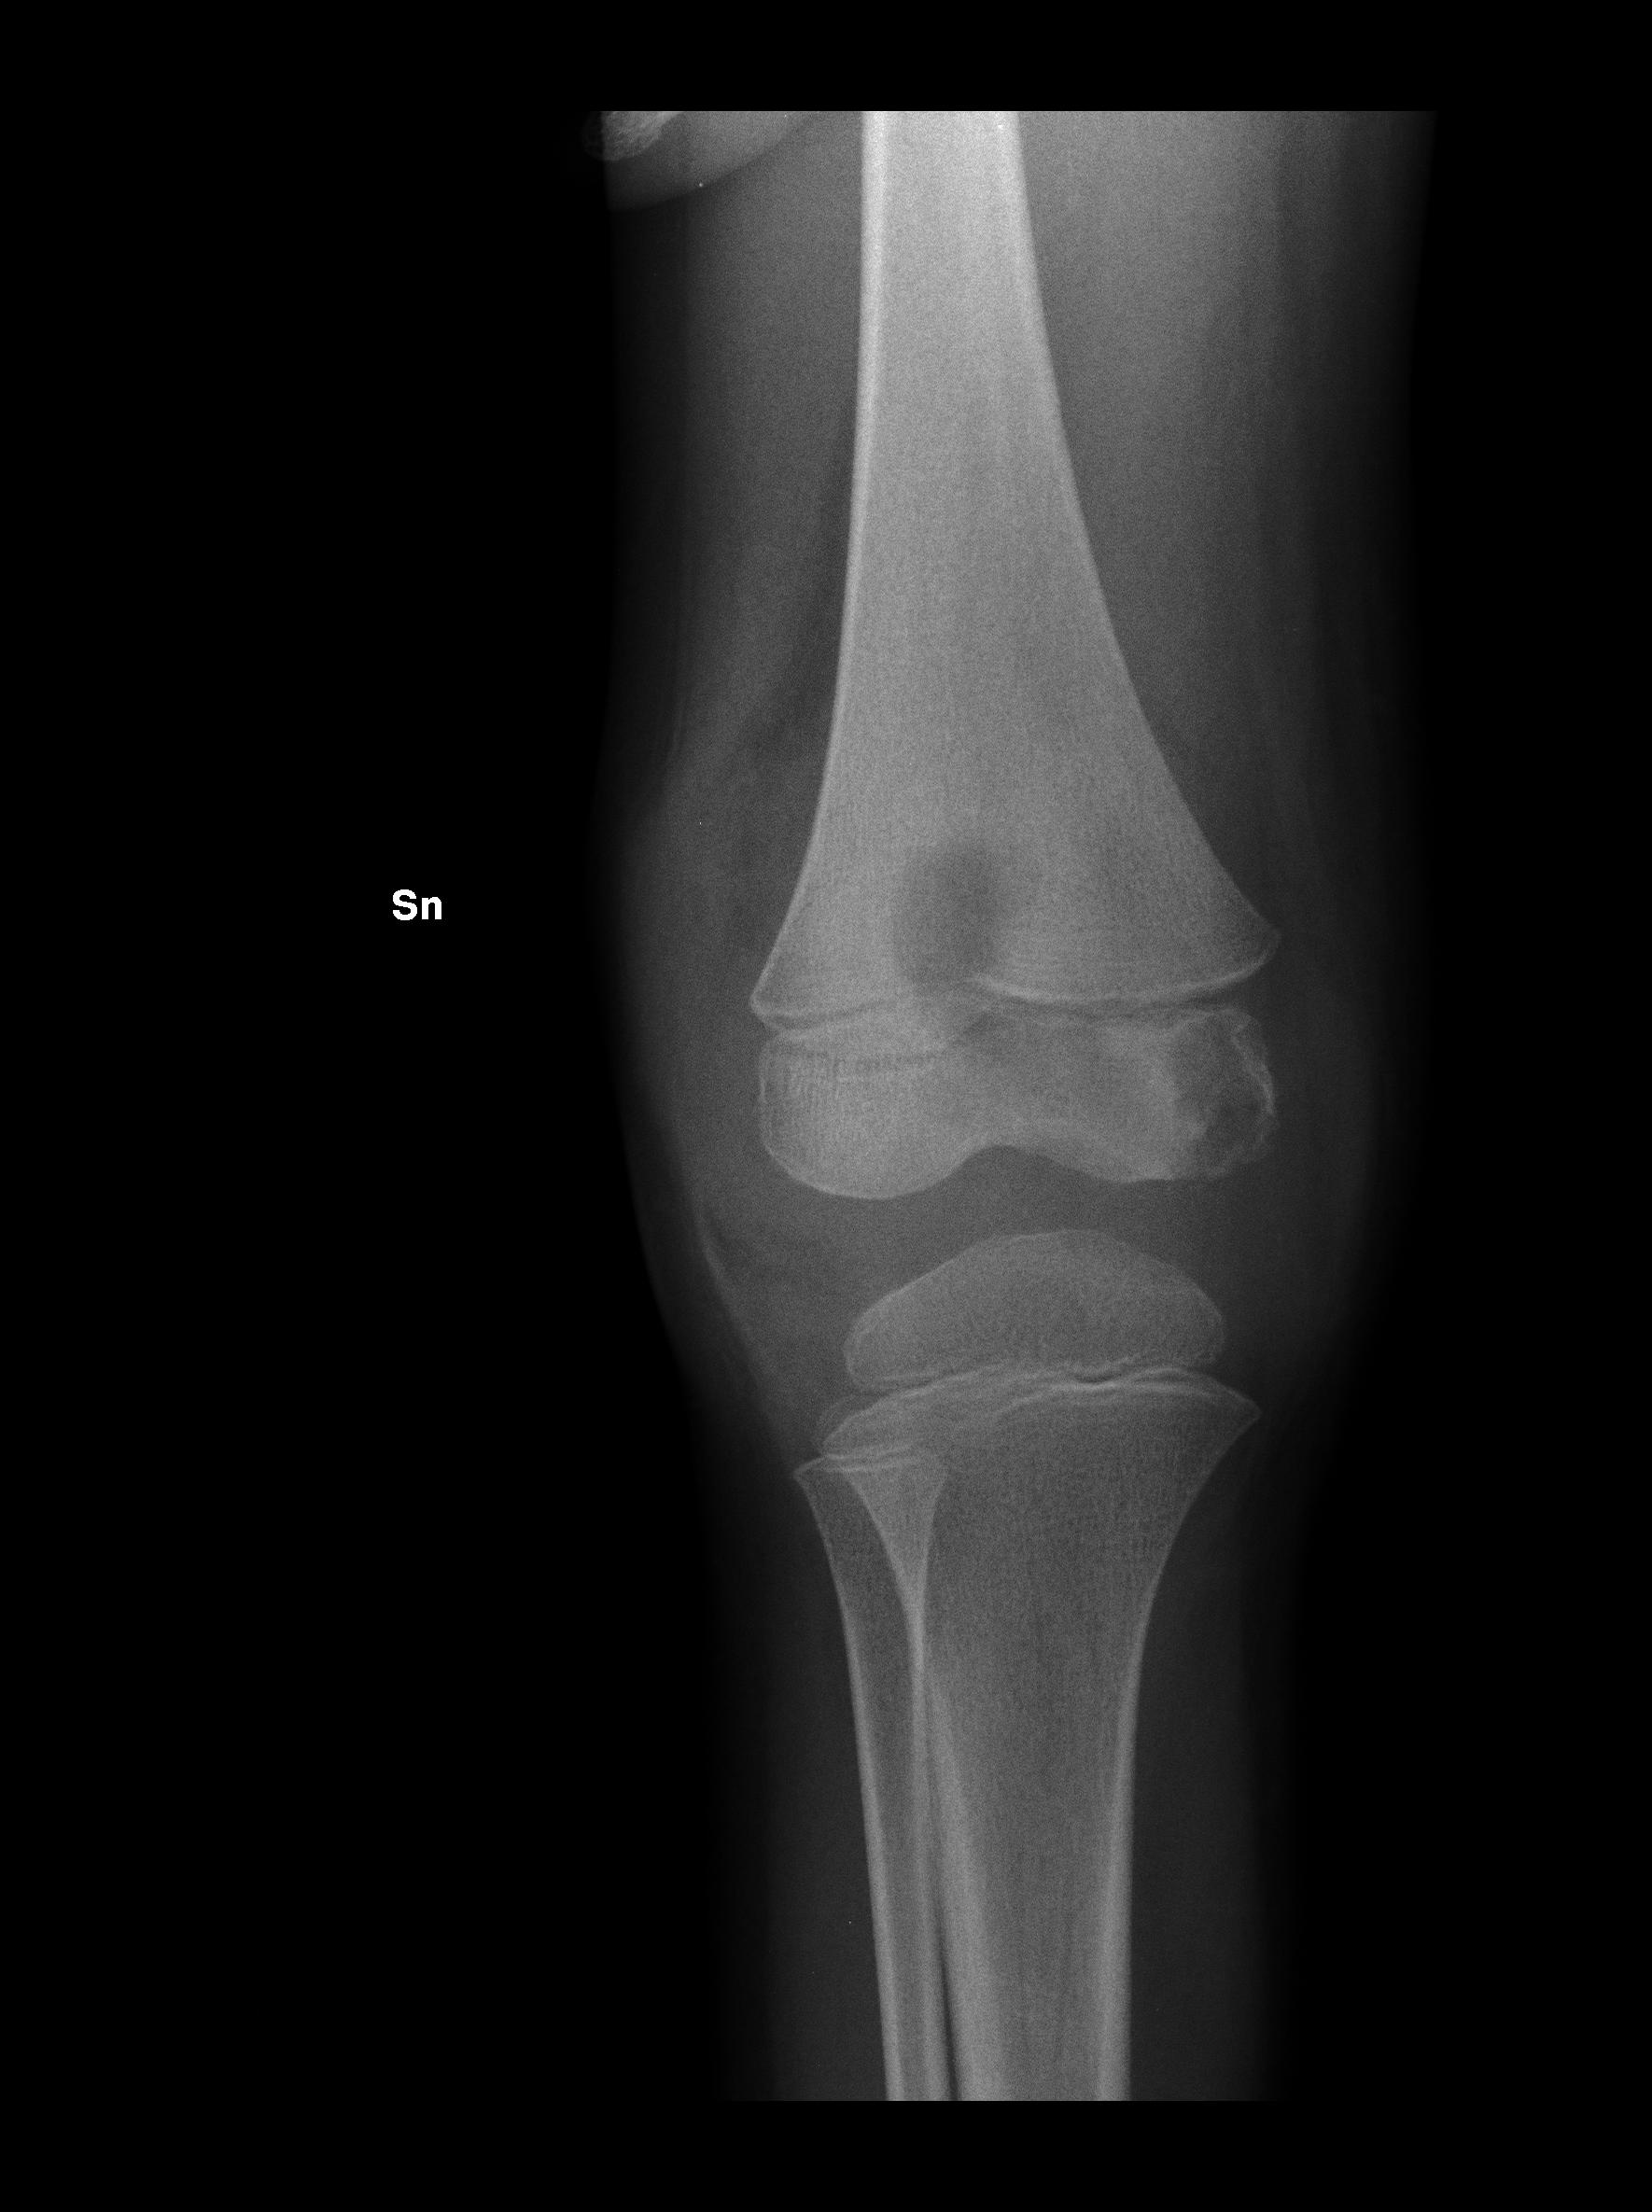

In altri 5 pazienti � stato isolato Staphylococcus aureus, ma in questo caso le complicanze sono state meno invasive e severe in paragone a quelle provocate dallo SBA. Infatti pazienti con infezione da SBA documentata hanno presentato esiti a distanza; ad esempio il paziente con fascite necrotizzante (Figura 1) � stato sottoposto a un trapianto di cute. In un solo caso � stato isolato lo pneumococco, responsabile di una osteomielite�(Figura 2).

Figura 2. Osteomielite post-varicella da pneumococco